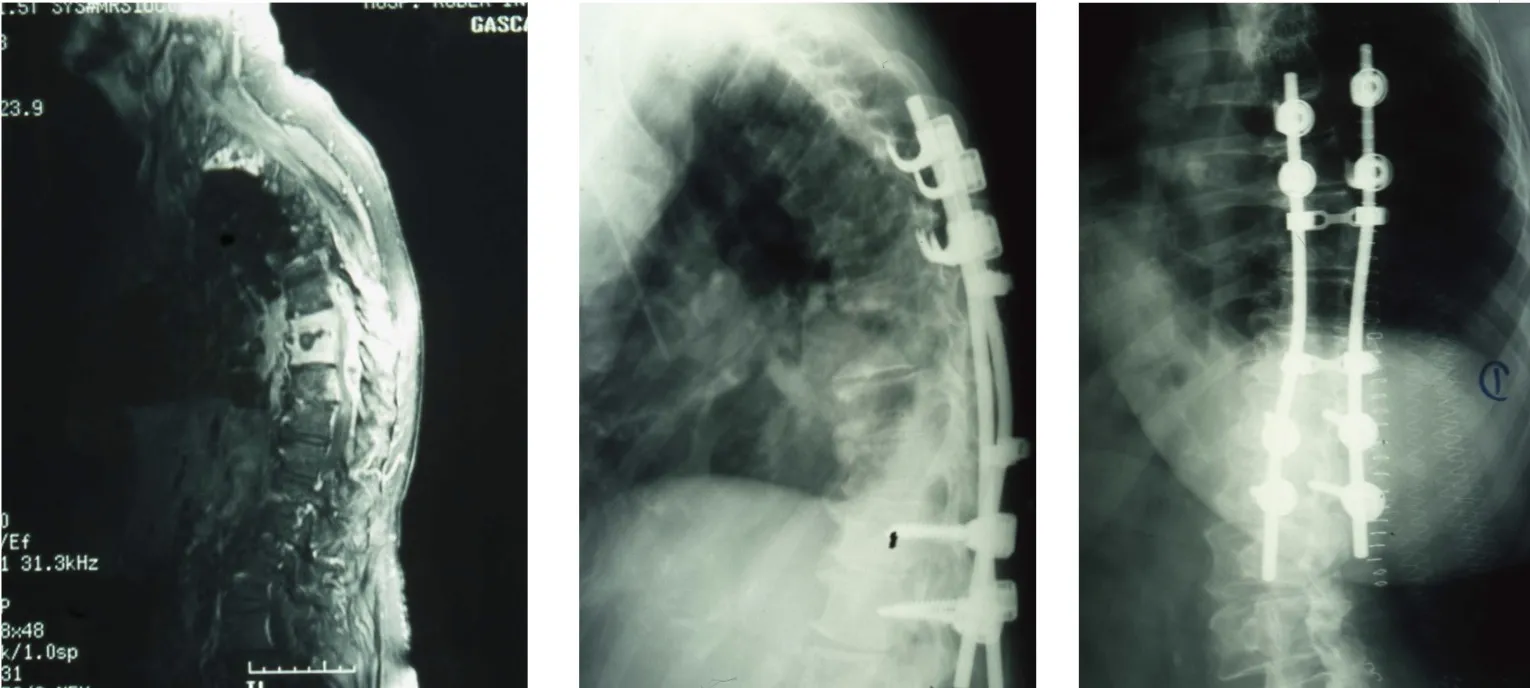

Técnicas quirúrgicas y resultados

Los estudios han demostrado que los abordajes dirigidos al foco infeccioso obtienen mejores resultados que las técnicas de descompresión simple:

- Laminectomías descompresivas sin fusión: resultados satisfactorios en 57-66% de los casos. Esta técnica, consistente en retirar las láminas vertebrales posteriores sin estabilizar, presenta resultados subóptimos.

- Desbridamiento y fusión posterior: acceso por la parte posterior de la columna con limpieza del foco y estabilización mediante tornillos pediculares. Resultados exitosos en el 97% de los casos.

- Abordaje y fusión anterior: acceso directo al foco infeccioso por delante, permitiendo una limpieza exhaustiva y colocación de injerto o caja intersomática. Resultados exitosos en 82-100% de los casos.

Estos datos confirman que el tratamiento quirúrgico debe ser agresivo en el sentido de abordar directamente el foco infeccioso y proporcionar estabilización adecuada, evitando técnicas de descompresión simple que han demostrado resultados inferiores.